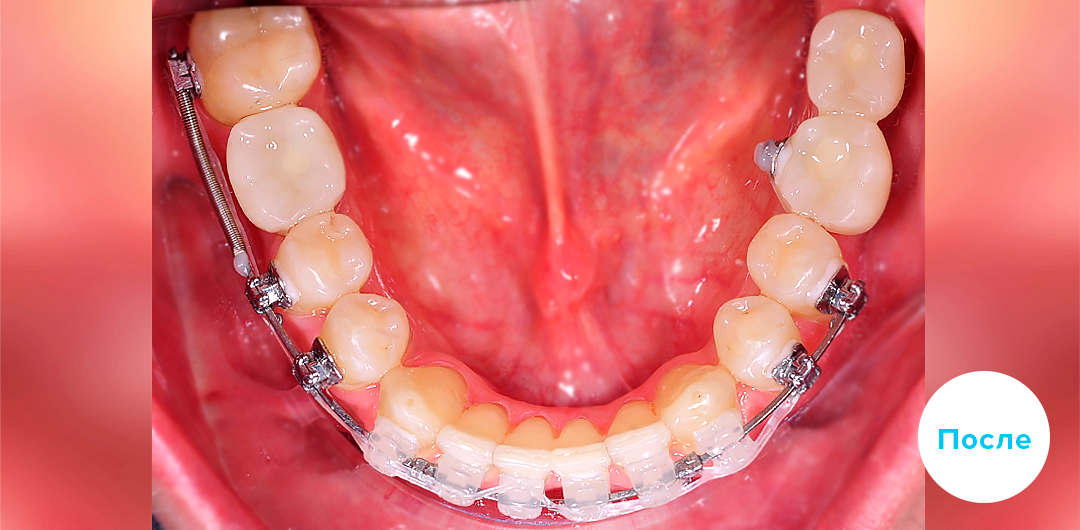

Результаты лечения